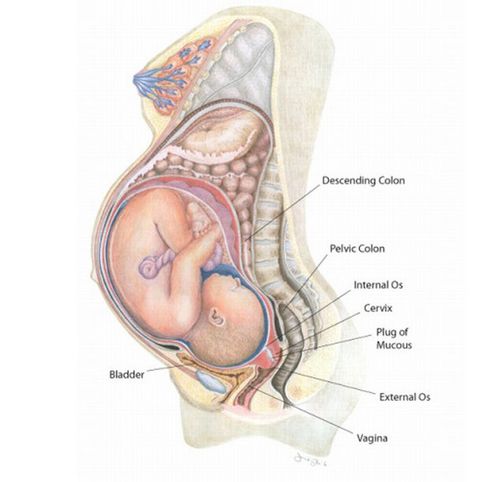

Як все влаштовано

У цервікальному каналі шийки матки секретується слиз. Залежно від періоду життя жінки ця слиз змінює свої властивості:

на рівні зміни гормонального фону келихоподібних клітини в шийці матки (цервікальному каналі) продукують скупчення в'язкого слизу.

До складу цієї слизу входять простагландини, імуноглобуліни, лізоцим і муцин, які мають бактерицидний ефект і захищають плід від проникнення мікробів і інфекцій. Виходить своєрідна пробка.